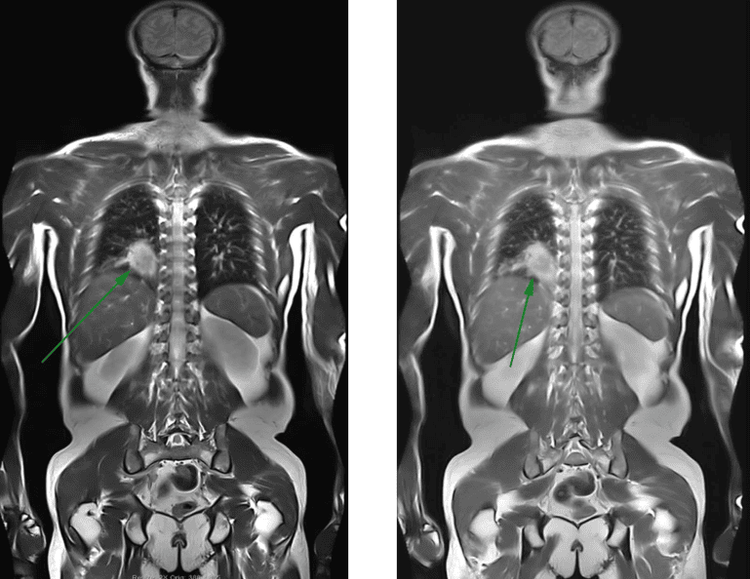

Chụp cộng hưởng từ toàn thân là kỹ thuật đang được sử dụng phổ biến trong chẩn đoán hình ảnh và điều trị bệnh vì có độ chính xác, chi tiết cao. Hiện kỹ thuật này đang thể hiện được vai trò quan trọng trong đánh giá tổng quát tình trạng sức khỏe, chẩn đoán, sàng lọc sớm bệnh ung thư.

Đây là kỹ thuật chẩn đoán hình ảnh công nghệ cao, ứng dụng công nghệ quét 3 chiều toàn bộ cơ thể, cho hình ảnh có độ sắc nét, tương phản cao, rõ ràng và chi tiết. Vì thế, các tổn thương lớn, nhỏ ở từng cơ quan, vị trí cần khảo sát đều được hiển thị rõ ràng. Đồng thời, bác sĩ cũng có thể sử dụng hình ảnh chụp MRI để tái tạo 3D, từ đó nâng cao hiệu quả trong chẩn đoán và điều trị bệnh.

• Người đang theo dõi điều trị ung thư: Chụp MRI nhằm đánh giá mức độ ung thư; khả năng di căn trên toàn bộ cơ thể; kiểm tra các tổn thương nguyên phát, thứ phát; đánh giá tiến trình đáp ứng điều trị ung thư,...